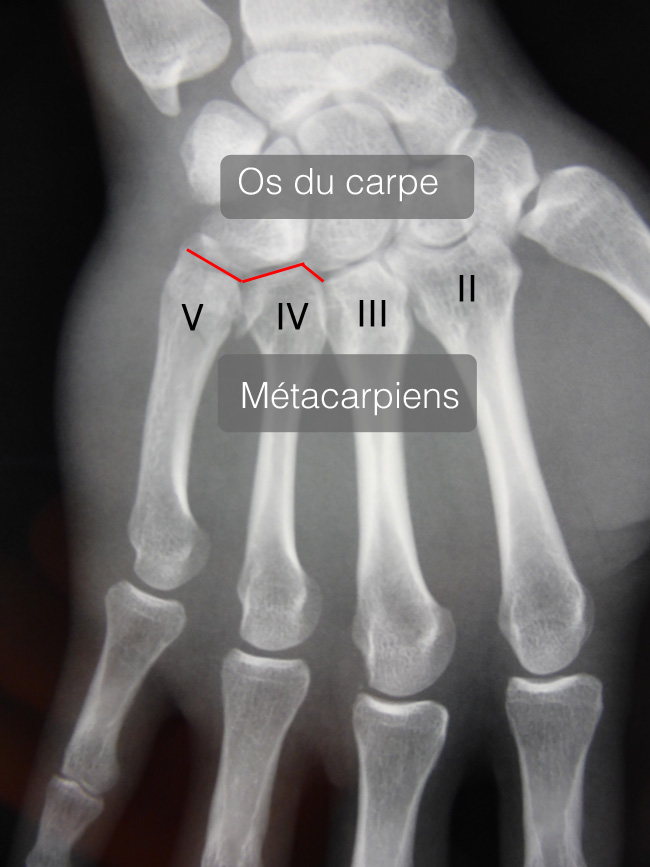

Les articulations carpométacarpiennes relient le poignet avec la main. Sur le plan anatomique, ce sont des articulations entre les os du carpe et la base des métacarpiens.

Les articulations des 5 eme et 4 eme métacarpiens sont de loin les plus souvent atteintes et les plus graves.

Il est important de préciser combien de métacarpiens sont atteints et s’il s’agit de fractures simples, fractures articulaires ou fractures luxations.